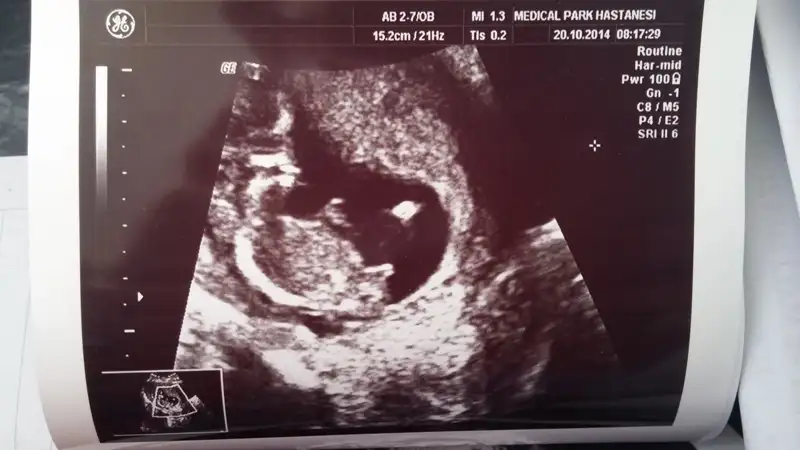

% 90 erkekArkadaşlar cinsiyet yorumu yapabilecek var mı? Lütfen yardım !!

Pipiyok büyük ihtimal kız dedikoydum göremediler pozisyonu uygun değil dediler bi kaç kişi kız dedi

hayırlı olsun cnm şanslı kadınların kızı olur derler bizde rabbim önce hayırlısını ve sağlıklısını versin tabiPipiyok büyük ihtimal kız dedi

Diğer ultrason görüntülerini atıyorum, lütfen bide bunlara bakarmısın?

Eki Görüntüle 1277161 Eki Görüntüle 1277162